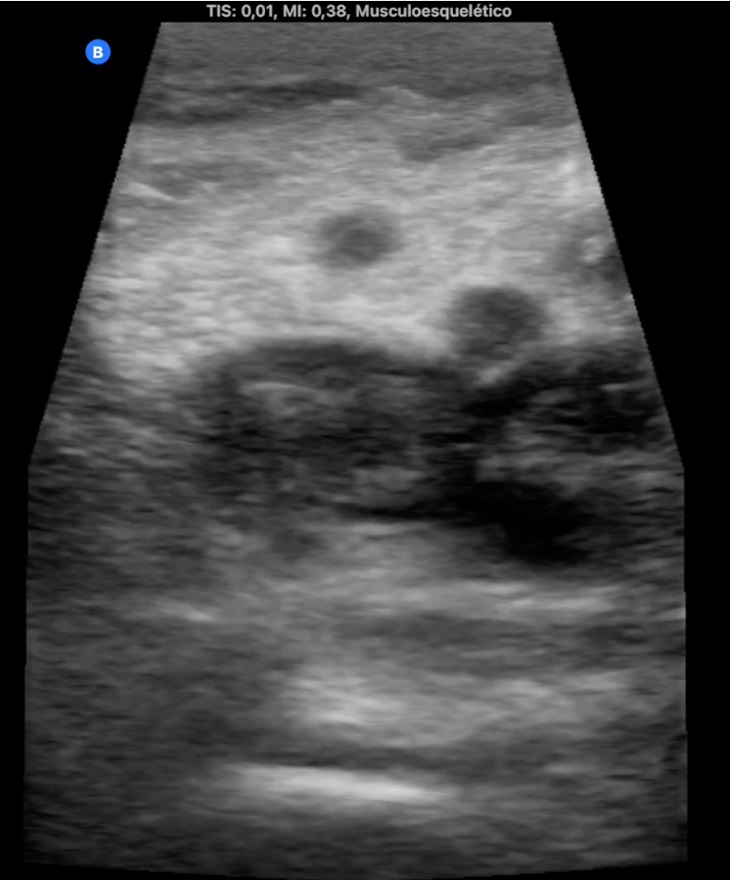

Hombre de 68 años con antecedentes de hernia de hiato/gastritis/úlcera duodenal, ex fumador desde hace 9 años y colelitiasis. Acude por edema y empastamiento de MID de 4 días de evolución (Imagen 1). Pérdida de peso de 5 kg en 2 meses. Analítica 20 días antes antes con Hb 14, LDL 150 y GGT 59, resto normal.

Ocupación de espacio con trombo venoso ecogénico desde poplítea hasta tercio superior, así como safenas externa e interna (imagen 2 femoral profunda e imagen 3 safena mayor). Lesión isoecogénica en segmentos hepáticos V/VI de 6,65 x 5,87 cm (imagen 4).